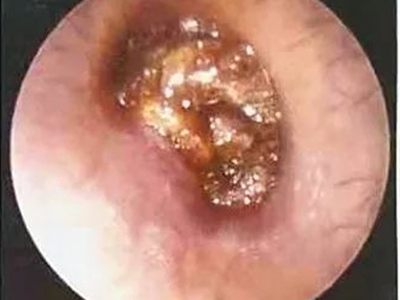

外耳道耵聍栓塞耳内黄褐色块状物图

外耳道耵聍栓塞患者外耳道分泌出黏性物质,不断堆积后形成黄褐色块状物,局部受到刺激后有出血症状,硬块表面呈鲜红色,伴有不同程度的疼痛。